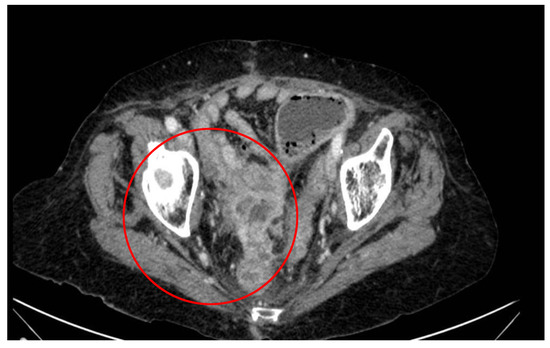

2. Case Report and Evolution